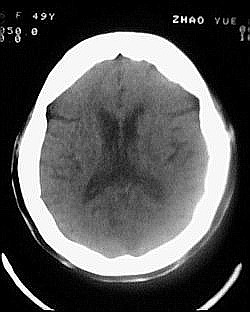

患者/49y/ 女/4年前有脑梗, 现因右侧肢体无力来院做ct扫描 ! 老师们看看这骨头有事吗?钙化点是什么原因呀??

1.颅骨对称性、形态规整性增厚,应属发育异常。四叠体池左后侧单发点状钙化,无其他阳性表现,多属正常,不需要过多关注。

2.双侧基底节区域多发性梗塞灶。

1、多发腔隙性脑梗塞是肯定的了。

2、颅骨形态规整性的增厚,密度增高,有无骨髓方面的疾病,建议骨髓穿刺。

不除外发育变异哈。

1.双侧基底节区腔梗。

2.颅骨内外板广泛性增厚,板障狭窄甚至消失,双侧对称。无明显相应临床症状。考虑“泛发性骨皮质增厚症”。可进一步检查下颌骨及管状骨骨干。(下颌骨骨小梁增多、密集,密度增高亦为本病特点,管状骨骨干皮质向内增厚引起骨皮质厚度增加,骨密度增浓、髓腔狭窄但不消失,骨干周径较少增加)。与石骨症鉴别,后者很少影响颅盖骨和下颌骨,管状骨改变主要累及干骺端和骨骺,而骨干皮质较少增厚,椎体和髂骨翼有特征性表现。